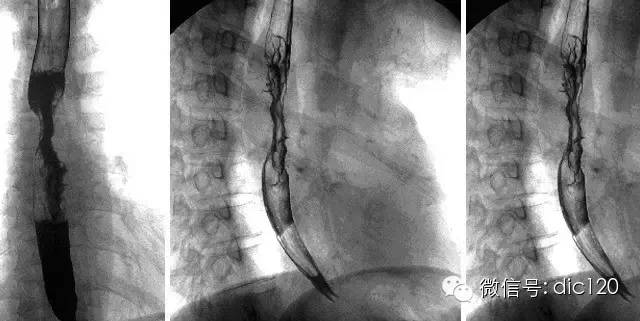

【影像表現】 CT:表現現為食管壁明顯增厚,管腔狹窄;食管與周圍結構分界不清食管吞鋇:食管中段充盈缺損,管腔不規則狹窄,管壁僵硬,粘膜糾集破壞,與正常食管壁分界清晰。

【診斷】 病理診斷:食管(中下段)高-中分化鱗狀細胞癌,侵及食管壁全層。(圖1.2)